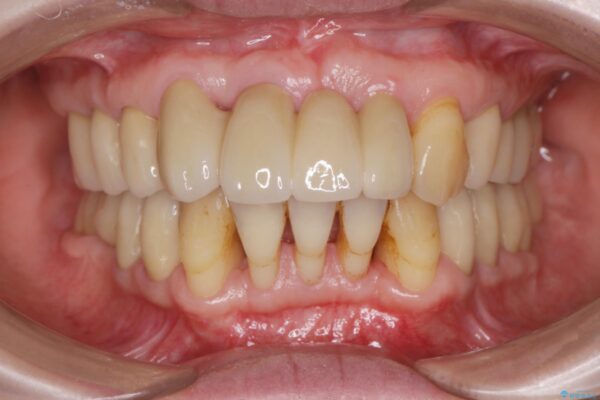

治療後

歯の総合的なマネージメントを行う包括的歯科治療の実践[ 歯周病・矯正・セラミック補綴 ] 治療後画像 歯の総合的なマネージメントを行う包括的歯科治療の実践[ 歯周病・矯正・セラミック補綴 ] 治療後画像 歯の総合的なマネージメントを行う包括的歯科治療の実践[ 歯周病・矯正・セラミック補綴 ] 治療後画像 歯の総合的なマネージメントを行う包括的歯科治療の実践[ 歯周病・矯正・セラミック補綴 ] 治療後画像

治療を終えて

治療期間は長期間になりましたが、歯が非常に磨きやすくなり、見た目も改善したことで審美性を大きく改善することができました。